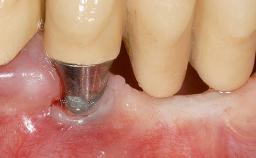

A 30-year-old woman was referred by her general dentist for evaluation of an esthetic complication related to previous implant treatment for congenitally missing maxillary lateral incisors. The patient’s chief complaint was the inadequate esthetic appearance of her smile. The case demonstrates the use of a combined approach to achieve optimal results. Two different flap designs - a tunnel technique and a coronally advanced flap - are employed based on the surgical objectives for the affected site.

Type of Implants Two-Piece

Attachment Two-Piece

Abutment Type Standard